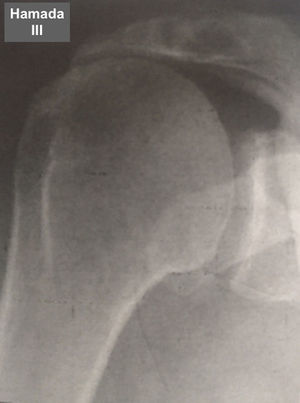

Fue elaborada por Hamada (tabla 6 y figs. 7–11) para describir el tipo de artropatía en roturas masivas del manguito de los rotadores. Utiliza la radiografía convencional y las características de la articulación glenohumeral y el ascenso de la cabeza del húmero para determinar el grado de la lesión. Muestra una correlación quirúrgica y radiológica de cerca del 80%10.